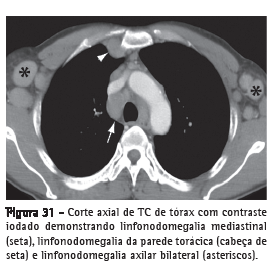

LinfonodomegaliaAumento de volume de linfonodo de qualquer etiologia, quando suas dimensões ultrapassam os limites considerados normais para a cadeia linfonodal em questão (Figura 31).(52,53) O termo "adenomegalia" não é um sinônimo recomendável, pois linfonodos não são estruturas glandulares verdadeiras. O termo "linfonodopatia" reserva-se para situações onde for possível identificar a doença linfonodal, como, por exemplo, quando se identifica necrose em seu interior.